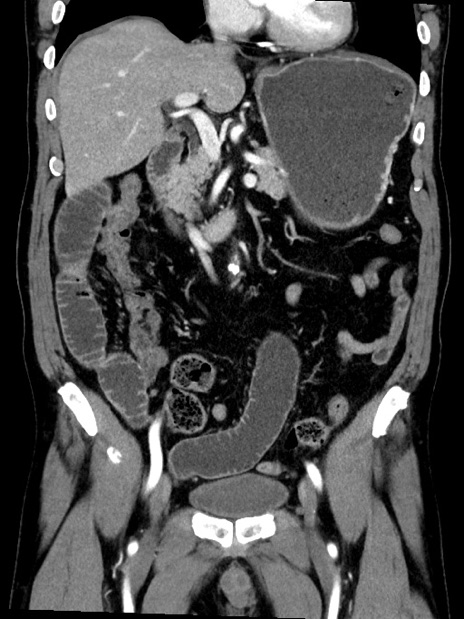

症例35(冠状断像)

【症例】70歳代 男性

【主訴】腹部膨満、嘔吐

【現病歴】昨日より腹部膨満感出現。本日増悪し、仙痛出現。嘔吐あり、受診。

【既往歴】糖尿病、胆摘後

【身体所見】BP 149/80mmHg、HR 74/min、BT 35.9℃、腹部:膨満、軟、圧痛なし。腸雑音減弱あり。上腹部正中切開瘢痕あり。

【データ】WBC 13500、CRP 1.72